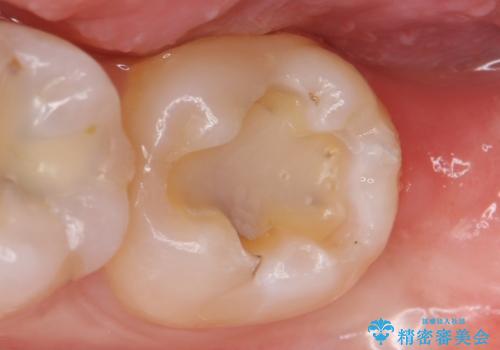

- 古い銀歯を白くしたいといらっしゃった方の症例です。

銀歯及び虫歯を除去後、セラミックインレーにて修復を行いました。

当院のセラミックインレーはemaxという強度と審美性に優れた材料を使用しています。

またプレス方式でインレーを製作しているため、削り出しで製作するCADCAMより優れた適合性も持ち合わせており、虫歯が再発しにくい修復物です。